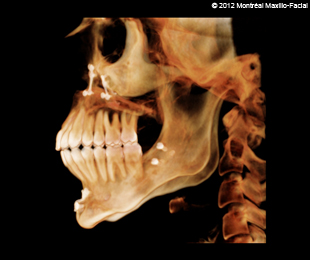

- 13 FÉVRIER 2012 - Rendez-vous avec mon chirurgien pour mes mâchoires